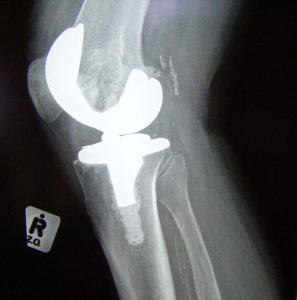

The surgery, which can be done in Pacific Surgical Center’s outpatient clinic, can improve quality of life and help regain or maintain mobility. Experts at the Mayo Clinic describe the process; “The procedure involves cutting away damaged bone and cartilage from your thighbone, shinbone and kneecap and replacing it with an artificial joint (prosthesis) made of metal alloys, high-grade plastics and polymers. In determining whether a knee replacement is right for you, an orthopedic surgeon assesses your knee’s range of motion, stability, and strength. X-rays help determine the extent of damage.”